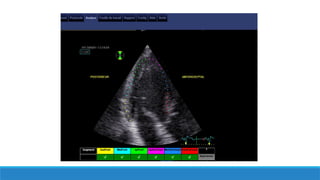

Le 2D strain VG: acquisitions

Qualité de l’image ++

Acquisition apicale non raccourcie

Bonne qualité de l’ECG++

Bonne détection des QRS

Enregistrement sur 3 cycles incluant 100ms avant QRS

IPS 50-80 /s (en fonction de la FC)

Inclure tout le volume cavitaire (systole et diastole)

Pas de variations de la FC (FA3D strain ou cycles équivalents)